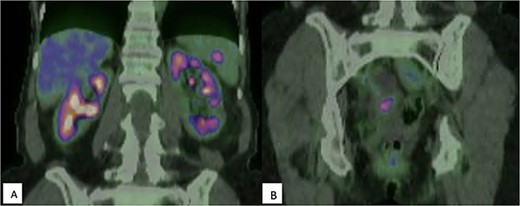

Surveillance CT 5 years after the completion of chemotherapy demonstrated bilateral pelvic adnexal ‘cysts’. These were investigated further with pelvic ultrasound and FDG PET, which demonstrated the large cystic lesions to have foci of moderate FDG avidity (SUVmax 4.0), with incidental finding of a moderately FDG-avid (SUVmax 5.6) lesion at the hilum of her spleen (Fig. 1).

(A) FDG-PET demonstrating moderately intense (SUVmax 5.6) uptake within the spleen, suspicious for malignancy; (B) Multicystic pelvic lesion with solid component (SUVmax 4.0).